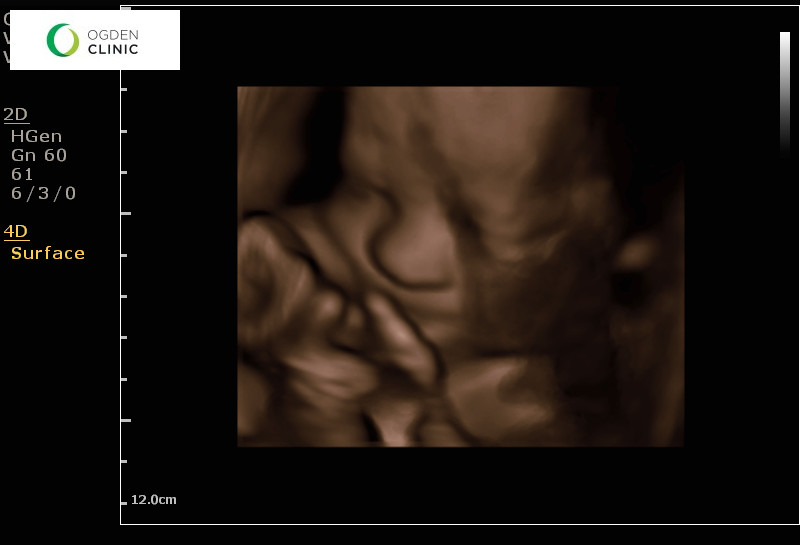

The day I was 30 weeks along, we got a 3D ultrasound of Baby!  I've never had one before, and man is this boy adorable!

He had his hands and feet up by his face.  He kept playing with his toes.  He's measuring about a week ahead of schedule and I think he looks like Henry!  We'll see when he pops out (as Hattie says) in less than two months!!!